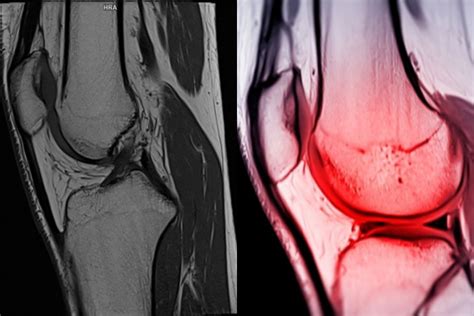

Po zranení je dôležité navštíviť ortopéda, ktorý určí rozsah poranenia. Na diagnostiku sa používa magnetická rezonancia alebo artroskopická operácia.

Priebeh operácie

Cieľom operácie je obnoviť stabilitu kĺbu, rozsah pohybu, silu a funkciu. Lekári používajú rôzne techniky rekonštrukcie ACL, ktoré sa líšia vo výbere štepu a vo fixácii v kolennom kĺbe.